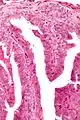

乳突状汗腺瘤

乳突状汗腺瘤(英語:),也成乳头状汗腺瘤(英語:),是一种界限清晰的乳腺组织异位肿瘤,经常发现于大阴唇。

| 显微镜下的乳突状汗腺瘤 | |

它通常为原发性肿瘤(非癌症性),但是因为其倾向于溃烂,常被诊断为外阴癌。从组织结构学角度,它通常被定义为与乳腺管内乳头状瘤一类的疾病[1]。